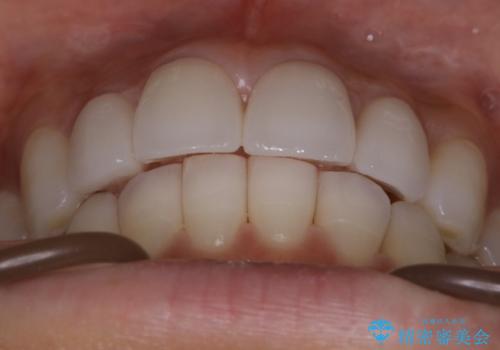

【非抜歯】噛み合わせを整えたい! インビザライン矯正

- 嚙み合わせのズレを主訴にご来院されました。

前歯・奥歯ともにセラミッククラウンで治療されている歯があったため、その歯にあまり影響が出ない範囲内で全体の噛み合わせが良くなるような動きを組み込んで治療を進めることとなりました。